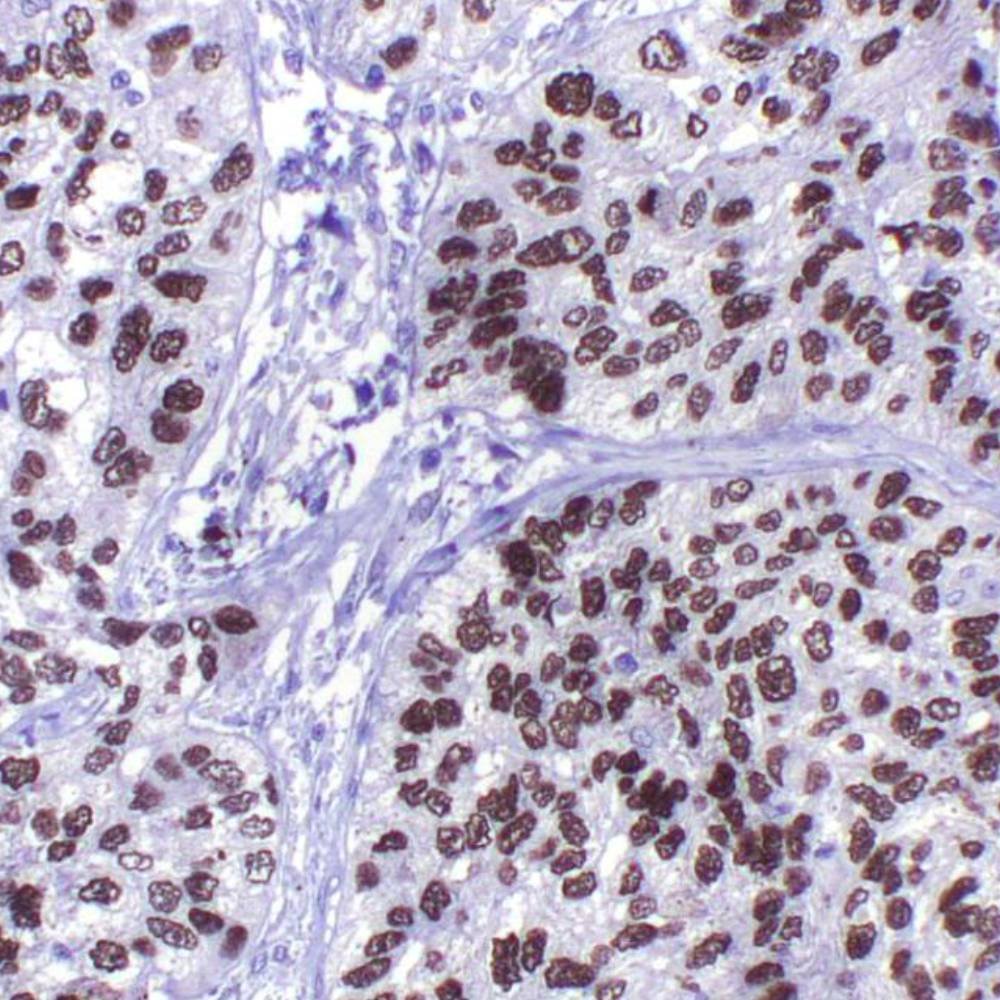

p40 antibody (antibody recognizing ΔNp63 only) is an isoform of p63, is thought to function as a stem cell factor, responsible for maintaining cells in an uncommitted state with regenerative potential—a role that may be recapitulated in tumors derived from these cells. p40 is normally expressed in the basal or progenitor cell layer of stratified epithelia (eg. squamous, urothelial, bronchial), basal cells of some glandular epithelia (eg. prostate), as well as myoepithelial cells of breast and salivary glands, trophoblasts and thymic epithelial cells. In tumor tissues, p40 expression is specific for squamous cell carcinoma. p40 is equivalent to p63 in sensitivity for lung squamous cell carcinoma, but it is markedly superior to p63 in specificity, which eliminates a potential pitfall of misinterpreting a p63-positive adenocarcinoma or unsuspected lymphoma as squamous cell carcinoma. p40 appears to be a more reliable marker for squamous cell carcinoma.

The rabbit monoclonal antibody p40 recognizes an epitope unique to the p40 protein and may have applications in cases where p63 has traditionally been used. p63 recognizes both the p63 and p40 proteins. As a result, p63 suffers from specificity limitations due to reactivity in a subset of lung adenocarcinomas (ADC). In contrast, p40 is selectively expressed in lung Squamous cell carcinoma (SqCC), offering an opportunity for improved specificity. p40 antibody recognizes an epitope unique to p40, which may result in diminished reactivity in lung ADC and increased specificity. Studies have supported routine use of p40 as an alternative for p63.